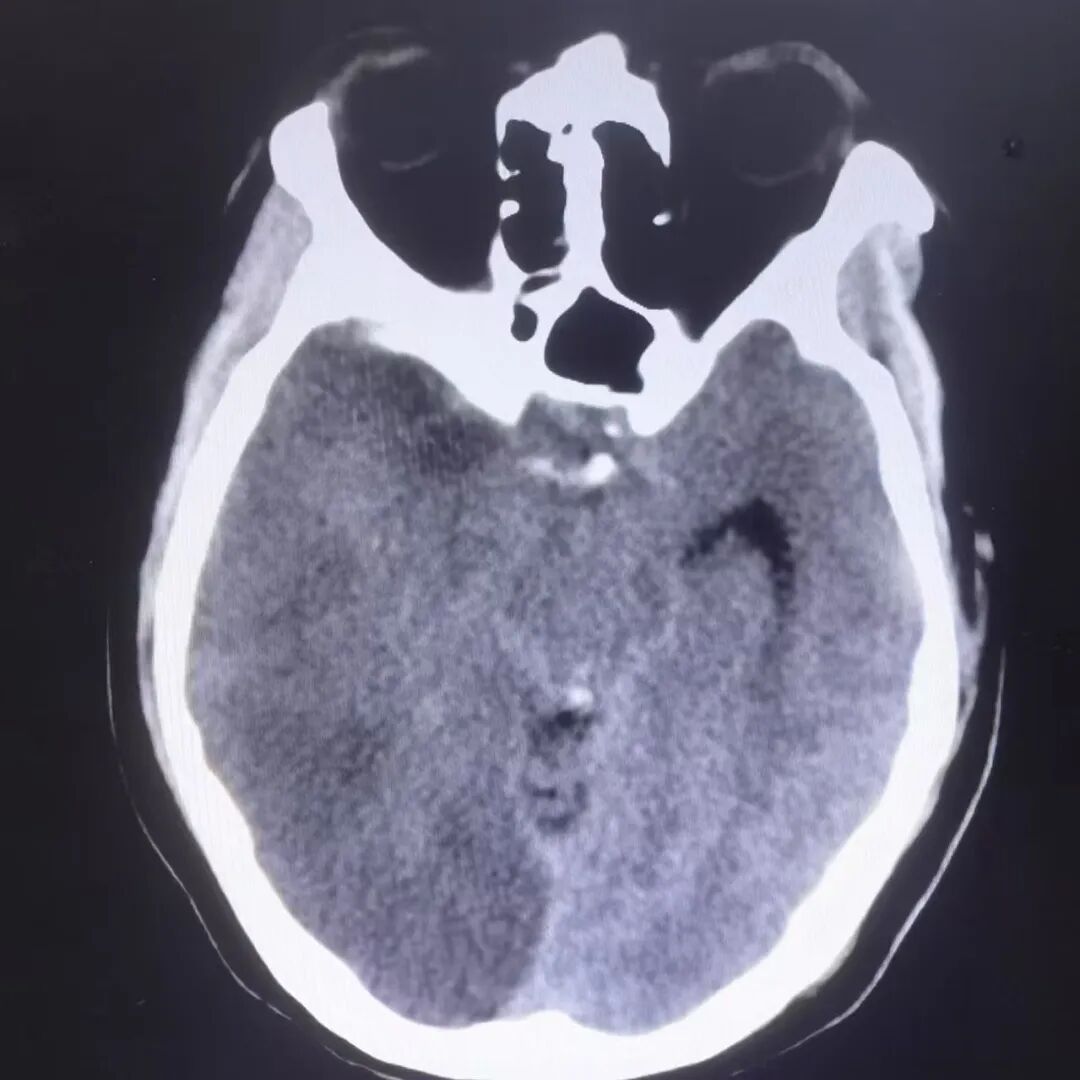

并发症处理:术后24小时患者精神状态差,意识模糊,查体昏睡,双侧瞳孔不等大,左侧直径3mm,右侧直径5mm,无光反应,左侧肢体肌力Ⅳ级,复查头颅CT水肿较重,请神经外科会诊,急诊行去骨瓣减压术。